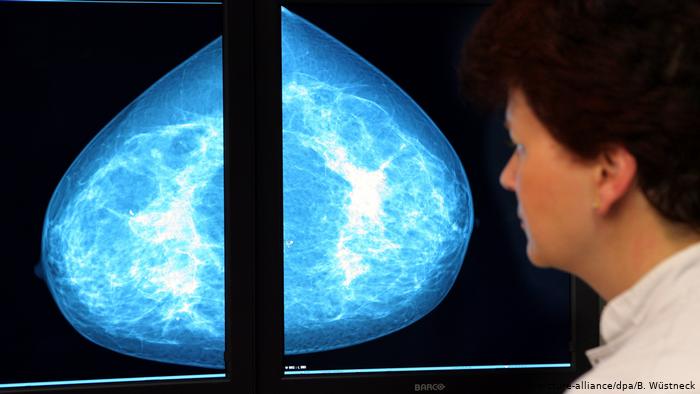

Në identifikimin e hershëm të kancerit të gjirit, të qafës së mitrës dhe zorrës së trashë, KE kërkon të arrijë që 90% e grupeve të popullsisë që duhet të bëjnë një skaner, të kenë mundësi ta bëjnë atë deri në vitin 2025. Edhe këtu ka dallime të mëdha mes vendeve anëtare. Nëse në Europën Perëndimore janë zhvilluar plotësisht programe të diagnostikimit, në Bullgari apo Greqi mungojnë programe të tilla.

Symbolbild Krebs Screening